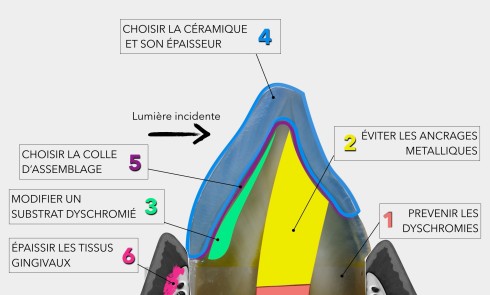

L’orientation thérapeutique de la prise en charge de la dyschromie s’appuie sur son diagnostic étiologique et répond à une méthodologie simple et applicable au quotidien.